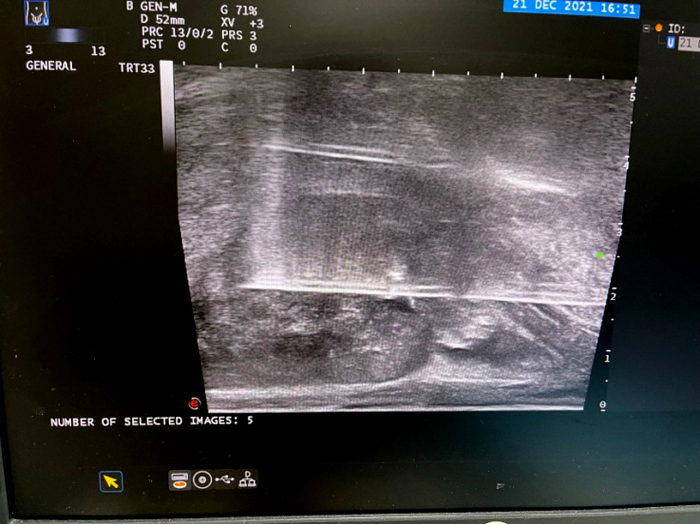

淋巴清掃術(shù)后,淋巴管囊腫置管引流并硬化